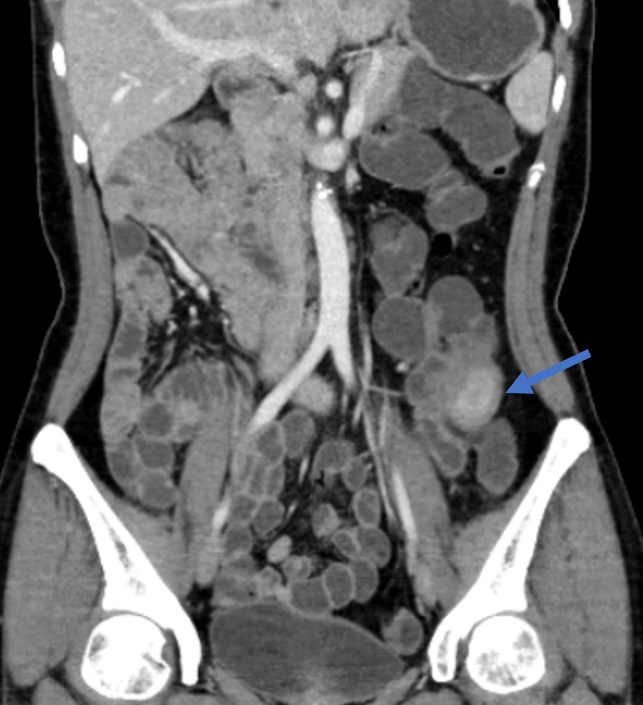

“正常人的空肠主要位于左中上腹(如图1),回盲部位于右下腹,而她的空肠在右上腹,回盲部范围位于左下腹的位置,因此定位及定性诊断应为回盲部的一个炎性肉芽肿(如图2蓝色箭头处)”赵雪松医生分析道。